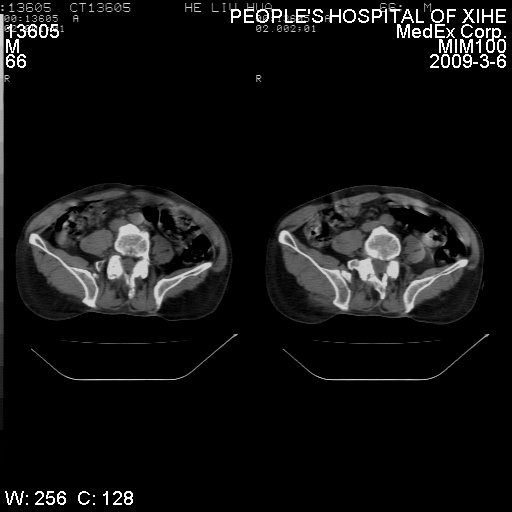

考虑----腰椎骶化-----退变-----椎管狭窄

腰骶椎退行性改变。

腰骶椎退行性改变,建议重建看看!

退行性变,椎体滑脱

腰椎滑脱并有退变

资料不清,考虑退变

退行性变,椎体滑脱。建议同椎体平行进一步扫描。